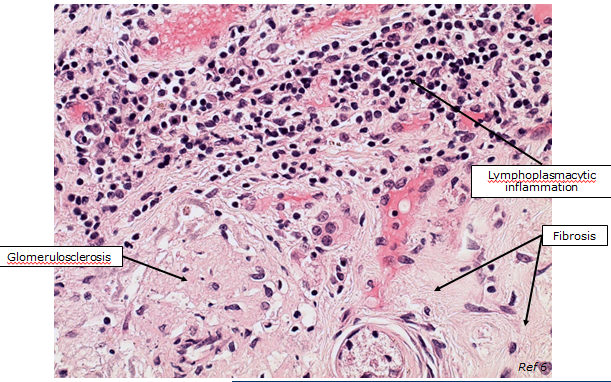

What can be seen here?

Diagnosis:

Bilateral severe chronic interstitial nephritis with severe fibrosis and tubular atrophy

(suspected leptospirosis)